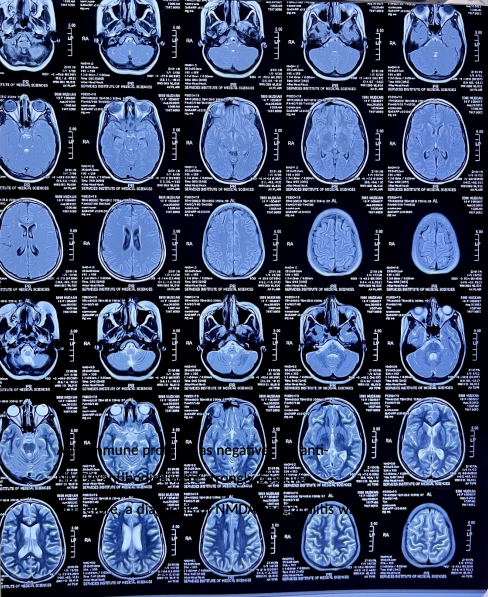

Case Study of NMDA Encephalitis in an 18-Year-Old Female With No Underlying Etiolog.

Sabina Nayab1, Qasim Bashir2, Adnan Aslam3, Amina Saeed khan4

Pages: 4-10